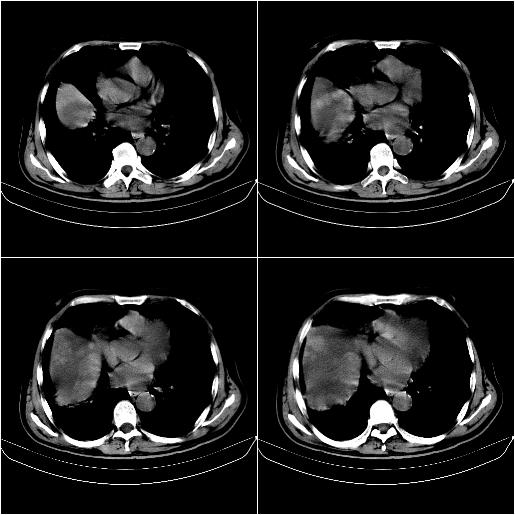

标题: CT21651:M,67Y,肝癌9月,介入术后3月。

m,67y,肝癌9月,介入术后3月。现腹胀、纳差、腹泻。

1)肝癌介入治疗术后碘油沉积不良。2)门静脉瘤栓形成,腹膜广泛性转移。3)肝硬化,脾大,腹水。4)慢性胆囊炎。